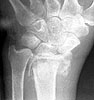

Seeking advice on management of 1 month old untreated distal radius fracture in non dominant hand of a 64 years old watchman. Pictures and xrays attached.

AP